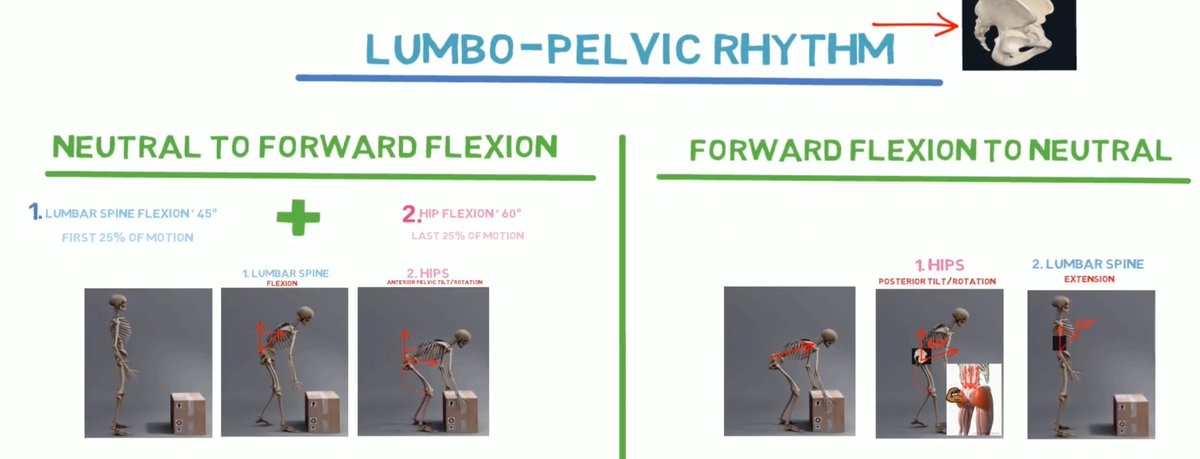

💢 ايش علاقة ألم أسفل الظهر مع العضلات الخلفية. ⁉️

وليش أحيانا تحس الألم في ظهرك ولكن المشكلة الأساسية عندك تكون في العضلات الخلفية وليس في الفقرات او عضلات أسفل الظهر.‼️ 🤷🏻♂️

💢 ايش علاقة ألم أسفل الظهر مع العضلات الخلفية. ⁉️

وليش أحيانا تحس الألم في ظهرك ولكن المشكلة الأساسية عندك تكون في العضلات الخلفية وليس في الفقرات او عضلات أسفل الظهر.‼️ 🤷🏻♂️